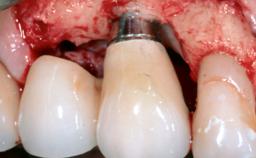

Due to their promising clinical performance, zirconia implants have recently become popular alternatives to titanium implants, particularly for areas with high esthetic demands (Holländer and coworkers 2016; Roehling and coworkers 2016; Lorenz and coworkers 2019). However, regardless of the reported high survival and success rates, zirconia implants were affected by peri-implant diseases over the short observation period, suggesting the importance of treating peri-implant diseases at zirconia implants (Becker and coworkers 2017). In their case, Frank Schwarz and Ausra Ramanauskaite present 3-year results following mechanical debridement alongside Er:YAG laser monotherapy.